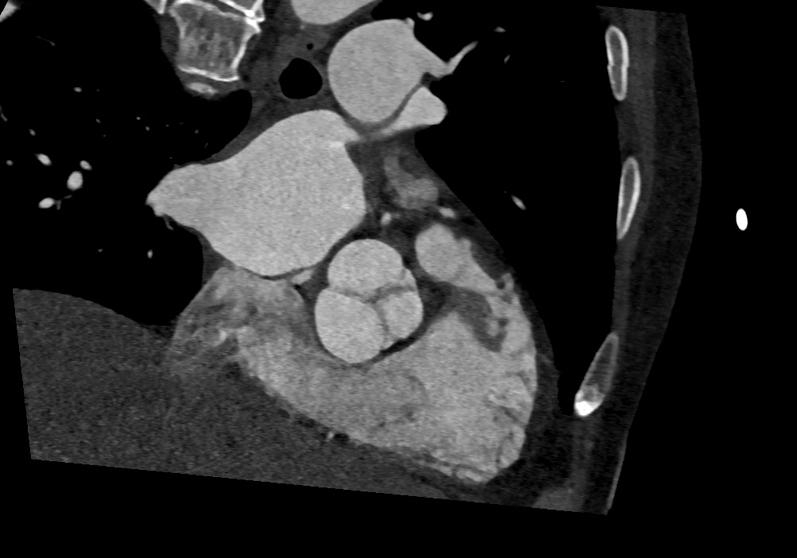

A man in his 70s presented with acute cerebellar stroke, breathlessness, and profound hypoxia worsened by the upright position. He tested positive for COVID-19, and computed tomography demonstrated a small pulmonary embolism, aorta dilation, and steep aortic angulation. Transthoracic echocardiography with a bubble study confirmed the presence of a PFO with right-to-left shunting during the Valsalva maneuver. Percutaneous PFO closure resulted in clinical improvement and resolution of hypoxemia.

This case highlights the interplay of PFO, aortic dilatation, and aortic angulation as key contributors to POS. Multimodal imaging is crucial for diagnosis and management.

一名70多岁男性因急性小脑卒中来诊,伴有呼吸困难,且直立位时严重低氧血症加重。他的新冠病毒检测呈阳性,计算机断层扫描显示有小的肺栓塞、主动脉扩张和严重的主动脉成角。经胸超声心动图造影检查证实存在PFO,在瓦尔萨尔瓦动作时存在右向左分流。经皮PFO封堵术使临床症状改善且低氧血症得到缓解。

该病例突出了PFO、主动脉扩张和主动脉成角之间的相互作用是POS的关键促成因素。多模态成像对于诊断和管理至关重要。